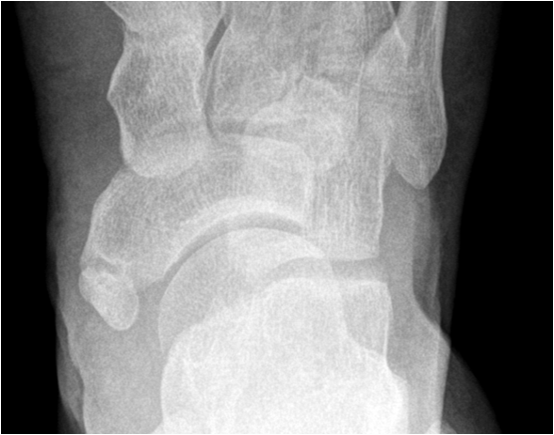

Image

Fig. 1. Os tibiale externum a frequent accessory bone medial to the navicular bone in the foot.

17.3.3. Dislocation and Subluxation

When the range of normal relationships for a particular joint is slightly exceeded, it is called a subluxation. When it is grossly exceeded, and the articulating structures are not in contact any more, it is called a dislocation. Joints most frequently affected by a luxation are shoulder, elbow, ankle, hip, and interphalangeal joints. Luxation will usually cause capsule and ligament disruption with soft tissue swelling and loss of fat planes. Associated avulsion fractures are frequently seen. As in fracture imaging exposure in two perpendicular planes are required to correctly visualize and describe a luxation or dislocated fracture.

Fig. 12. A) Complete dislocation with contraction in the elbow joint. Ulna and radius are both dislocated and dorsally displaced. B.) Anterior and inferior dislocation of the humerus.